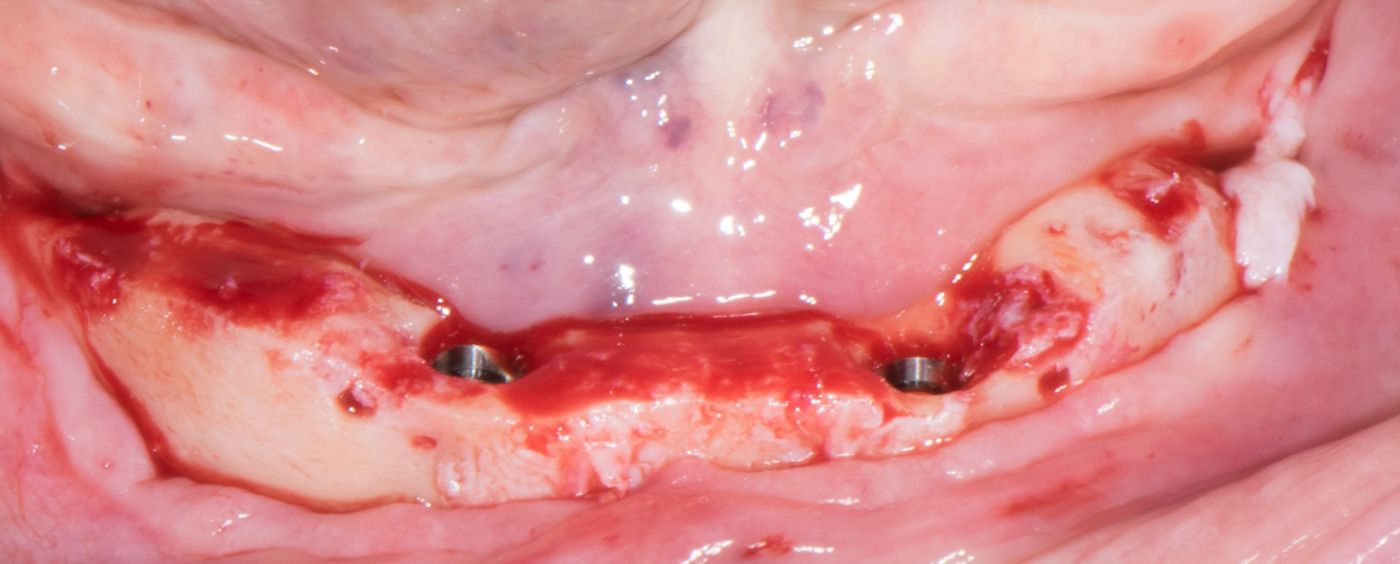

On the day of surgery two bites were taken: first with the guide for the pins for stable drilling (Fig. 9), then with the existing prosthesis (Fig. 10), for its correct conversion into an immediate restoration. The first mucosa-supported guide was used for drilling the sites for Template Fixation Pins (Fig. 11). Next, the guide was removed, the flap was raised, and the second guide was fixed with the pins at the corresponding sites (Fig. 12). Implant beds were prepared (Fig. 13-14) and Straumann BLT implants placed with a torque setting of more than 35 Ncm, following the protocol to allow correct subsequent SRA placement (Fig. 15-16). Bone around the implants was prepared with Bone Profilers for the same reason (Fig. 17). The crest was flattened (Fig. 18-19), SRA abutments were screwed to 35 Ncm (Fig. 20) and covered with healing caps, and the wound was sutured (Fig. 21).